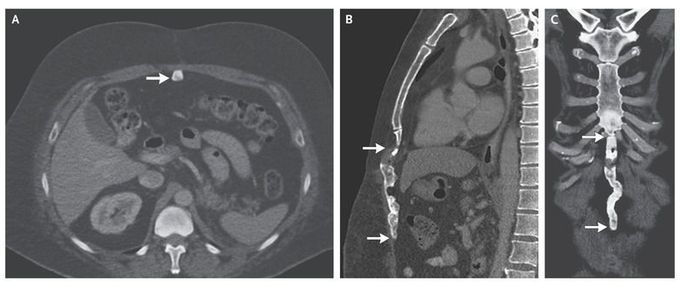

A 49-year-old man underwent computed tomography (CT) as part of routine follow-up after a left nephrectomy performed 2 years previously for renal-cell carcinoma. A healed vertical midline incision in the upper abdomen was found during a physical examination. CT of the abdomen revealed a vertically oriented, linear, calcified lesion in the incision scar on the anterior abdominal wall (Panel A, arrow), extending from the immediate subxiphoid region (Panels B and C, top arrow) to the umbilical region (Panels B and C, bottom arrow). This finding was consistent with heterotopic ossification, a subtype of myositis ossificans traumatica. Histologic evidence of osseous, cartilaginous, and occasionally myelogenous elements distinguishes this entity from dystrophic calcification. Although it is symptomatic only in rare cases, it may cause abdominal pain and discomfort; treatment in such cases consists of complete excision with primary closure. In this case, no further action was taken; however, the patient was advised to return for a follow-up visit.